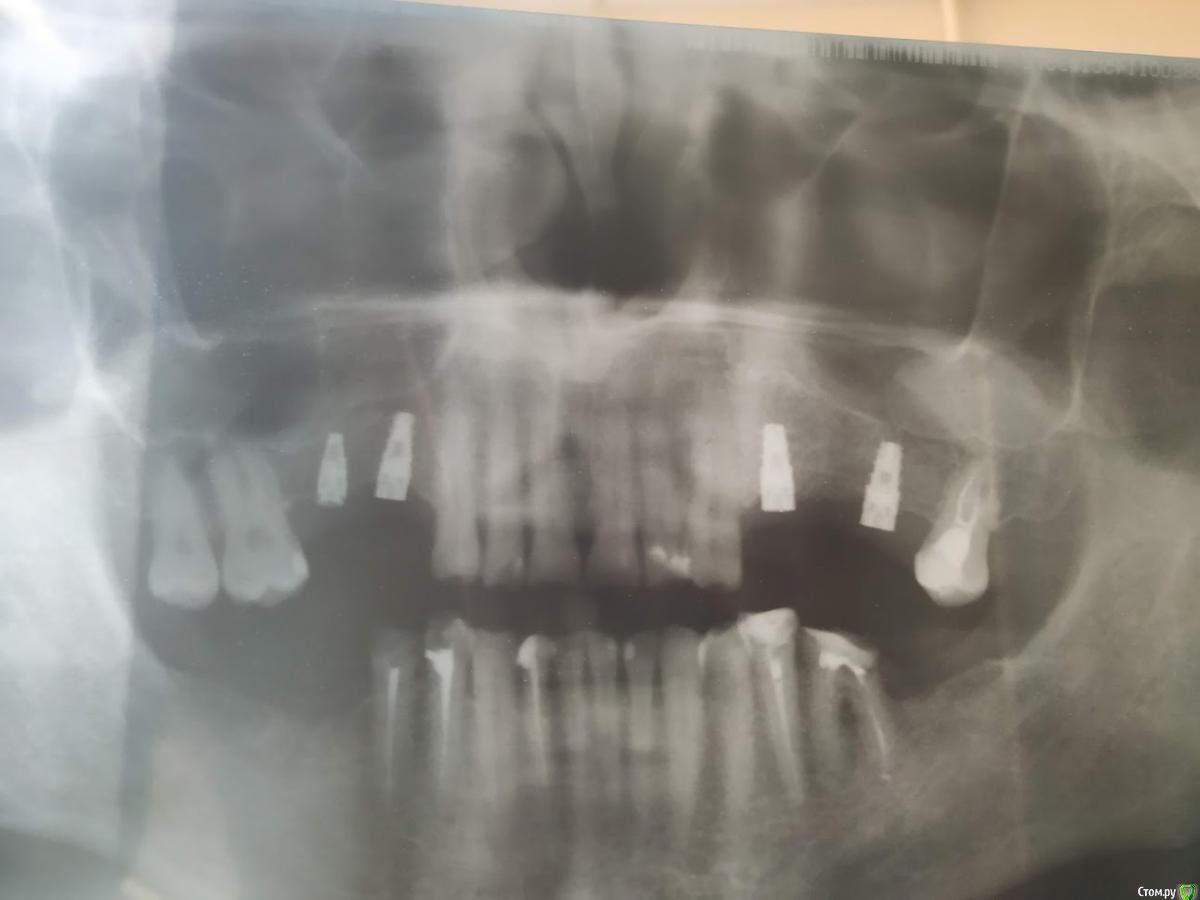

Валдемар Опубликовано 29 августа, 2019 Поделиться Опубликовано 29 августа, 2019 Добрый день,Уже был здесь, но прошлые явки и пароли забыл.12.04 операция 4 импланта20.04 вылез первый15.05 вылез второй26.08 удален 3ий28.08 удален 4ыйПотрачено 100тр, время и нервы. Возвращено 7200 за 2 импланта, за 2 которые удаляли деньги не вернули, так как не было показаний. А то что голова болит, переносица, лоб - ет не от этого. Удалил и всё прошло, кстати.Вопрос:1). Справа десны (кости) реально меньше чет слева. Что с этим делать. Как сделать чтобы кости хоть немного прибавилось? Без имплантации, просто кость с десной нарастить.2) 100% неприживаемости - ето как? Диабет, спид, гепатит по диспансаризации сдавал - отрицательно. Какие мои действия теперь? по новой имплантироваться и если опять не приживется, опять по новой? Ссылка на комментарий

Валдемар Опубликовано 31 августа, 2019 Автор Поделиться Опубликовано 31 августа, 2019 Я снимок после удаления не делал, но у меня реально справа десна тоньще раза в два. Там воспаление месяца два шло. В имплантацию больше не верю, вернее, боюсь. Боюсь нового стресса для организма. Верил в современную медицину, российскую, смотрел на людей с коленками кривыми, тазобедренными суставами проблемными, говорил че вы ждете, щас раз и коленку и тазобед сустав меняют и как новенький, а теперь понимаю, фиг там. Китайское что рибудь поставят, или руки у дохтора не оттудава, и всё, можно на костылях оставшуюся жизнь бегать...Потому люди до последнего и тянут. Ссылка на комментарий